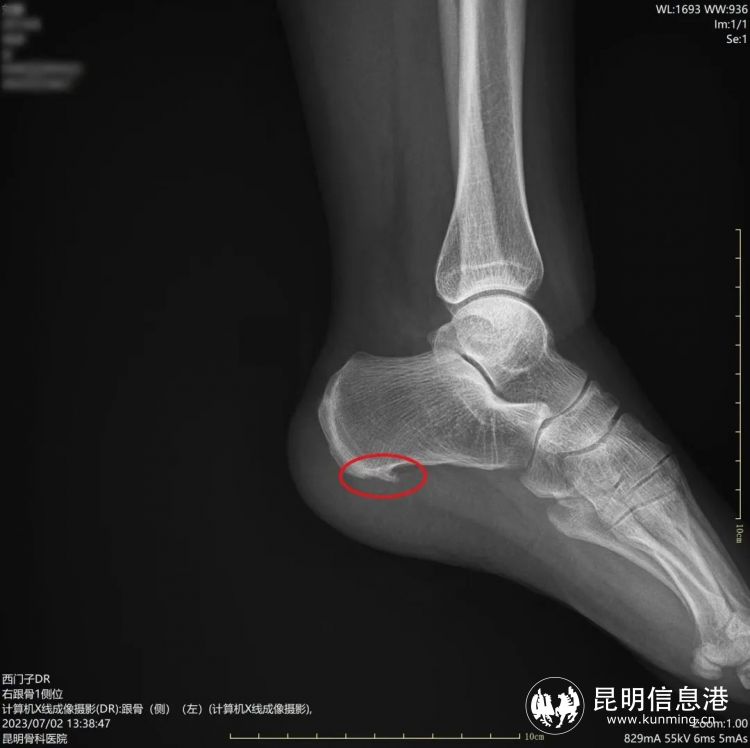

术前骨刺明显

“经检查发现刘女士不仅左足跟有跟骨骨刺,双足还有足底筋膜炎,本次微创手术只需在患者足内侧跟骨前结节处两侧各取一个0.2-0.5cm的小孔,建立镜下手术工作通道,就能在可视下磨除跟骨骨刺,筋膜松解,处理炎症组织。”昆明骨科医院手足显微外科主任李海波介绍说,这种新型的微创治疗手段对比起传统的治疗来讲有很大的优势,微创损伤小、恢复快、手术疼痛轻等特点,传统的跟痛症手术通常从跟骨内侧长斜形切口,长约5厘米,典型的“小手术、大切口”。